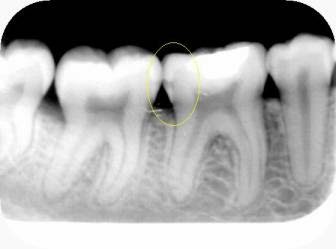

Los odontólogos podemos diagnosticar cualquier enfermedad que afecte tanto tejidos duros (dientes) como blandos (encías, lengua, labios, etc.) a través del examen clínico acompañado del examen radiográfico.

Examen radiográfico. Caries interproximal (entre dos piezas).